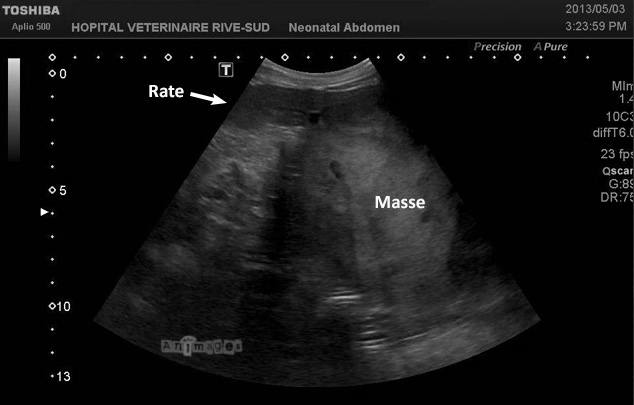

Eh bien, cette masse était…

[roulement de tambour] …de l’hyperplasie nodulaire avec hématome spontané ! Elle impliquait la rate que l’on aperçoit en continuité avec la masse sur la bande échographique ainsi que sur l’image CT (pour voir l’article initial, cliquez ICI).